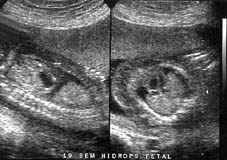

We present a case of recurrent hidrops fetalis, the diagnosis and management.

Presentamos un caso de hidrops fetal no inmune recurrente, idiopático, el estudio realizado y manejo del caso específico.